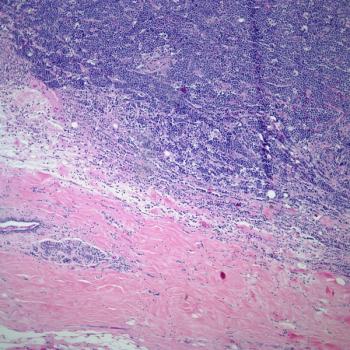

A 38-year-old man presents with abdominal pain and general malaise. What is your diagnosis?